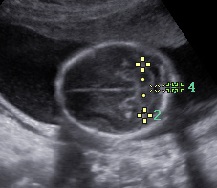

Las estructuras intracraneales después de la semana 18-20 del embarazo son muy características y permanecen visualmente invariables hasta el final del embarazo, solo modificando sus tamaños a medida que el feto crece. Esto es de gran ayuda ya que permite determinar la aparición de cambios que podrían sugerir desviación de la normalidad y aparición de una malformación congénita o lesión adquirida por eventos externos especialmente relacionados a infecciones y accidentes vasculares fetales.

Cuerpo calloso: es una estructura compuesta por haces nerviosos cuya función es la de conectar e integrar regiones corticales homólogas entre ambos hemisferios cerebrales. Su ausencia total puede conducir a problemas cognitivos y del desorrollo psicomotriz o pasar totalmente desapercibida. Su ausencia parcial, paradójicamente, se asocia con peor pronóstico. Como estructura ecográfica, es una de las más bellas que hay en el cerebro pero, para obtenerla se requiere pericia y muy buena resolución ecográfica. Sus alteraciones congénitas son diagnóstico de problemas primarios del desarrollo cerebral y se manifiestan con cambios indirectos en otras secciones cerebrales, especialmente ventriculomegalia.